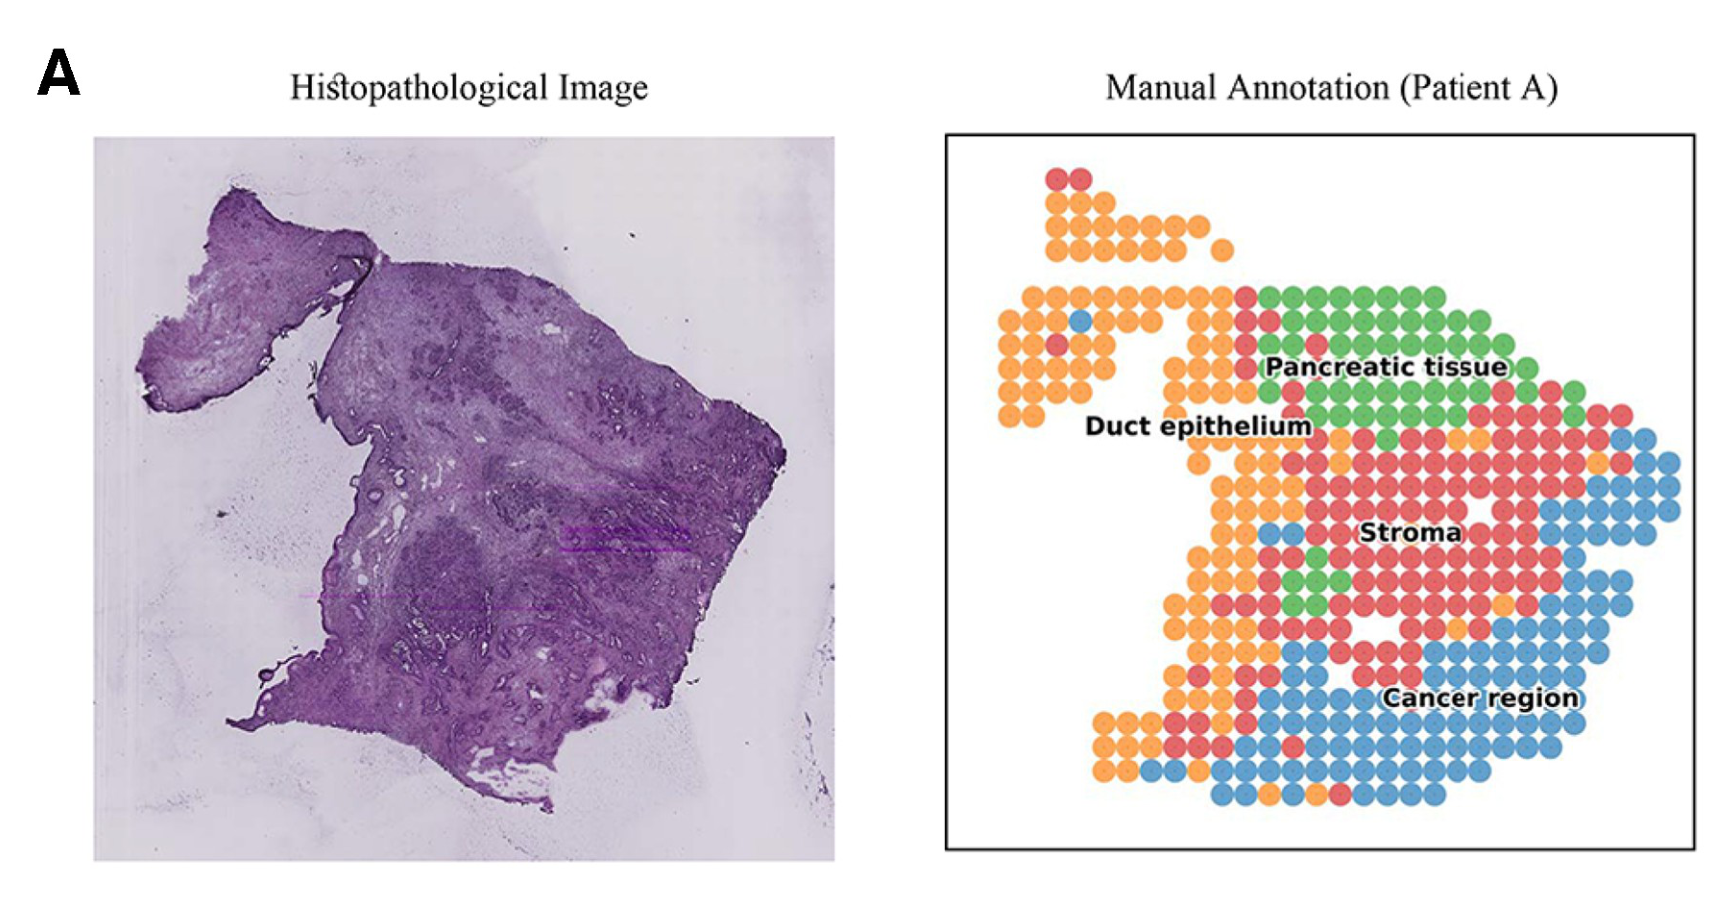

Chen N. et al. - 2024

How do different methods identify spatial domains?

Histological imageScatterplotSpatial Tissue Map

Juxtaposition : Small multiplesSuperposition

How are pathologist-defined tissue regions distributed across a cancer tissue section?

Histological image

Highlighting

How does the computational method identify cancer tissue heterogeneity?